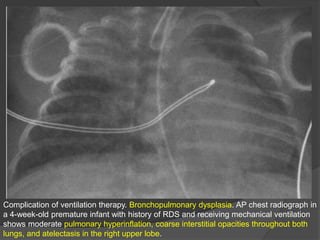

Complication of ventilation therapy. Bronchopulmonary dysplasia. AP chest radiograph in

a 4-week-old premature infant with history of RDS and receiving mechanical ventilation

shows moderate pulmonary hyperinflation, coarse interstitial opacities throughout both

lungs, and atelectasis in the right upper lobe.

Complication of ventilationtherapy. Bronchopulmonary dysplasia. AP chest radiograph in a 4-week-old premature infant with history of RDS and receiving mechanical ventilation shows moderate pulmonary hyperinflation, coarse interstitial opacities throughout both lungs, and atelectasis in the right upper lobe.